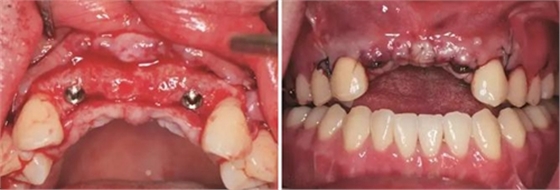

圖11 植骨后6月種植術(shù)前 圖12 種植術(shù)前翻瓣后見少量鈦釘螺紋暴露

圖13 取出鈦釘后 圖14 攜帶體示植體位置方向良好

圖15 種植術(shù)后 圖16 種植后嚴(yán)密縫合創(chuàng)口

(3)2015年2月:Onlay植骨后6月行種植手術(shù)

術(shù)前再次拍攝CBCT,顯示牙槽嵴寬度較植骨當(dāng)日有一定量的吸收,測(cè)量可用骨寬度,12位點(diǎn)為3.7mm-10.9mm,22位點(diǎn)為5mm-10.9mm。做術(shù)前準(zhǔn)備,用0.12%的復(fù)方氯己定漱口液含漱3次,每次15ml,含漱1min。采用無(wú)痛麻醉機(jī)(STA),復(fù)方鹽酸阿替卡因進(jìn)行口內(nèi)局部浸潤(rùn)麻醉,將麻醉藥物緩慢注入術(shù)區(qū)的牙槽嵴骨膜下方。翻瓣并剝離粘骨膜后充分暴露牙槽骨,取出先前固定骨塊的鈦釘,確認(rèn)植入位點(diǎn),小球鉆定點(diǎn),使用BEGO骨水平種植體及其配套器械(BEGO公司,德國(guó)),根據(jù)擬植入種植體長(zhǎng)度以及直徑大小,逐級(jí)備洞,植入2顆種植體,均為BEGO,RSX植體,直徑為3.75mm,長(zhǎng)度為15mm,獲得35Ncm以上植入扭矩,用種植體穩(wěn)定性測(cè)量?jī)xOsstell ISQ (Osstell公司,瑞典)測(cè)量ISQ值:12、22位點(diǎn)種植體均為79,種植體平臺(tái)位于骨下約1mm,術(shù)后上愈合基臺(tái),嚴(yán)密縫合創(chuàng)口。